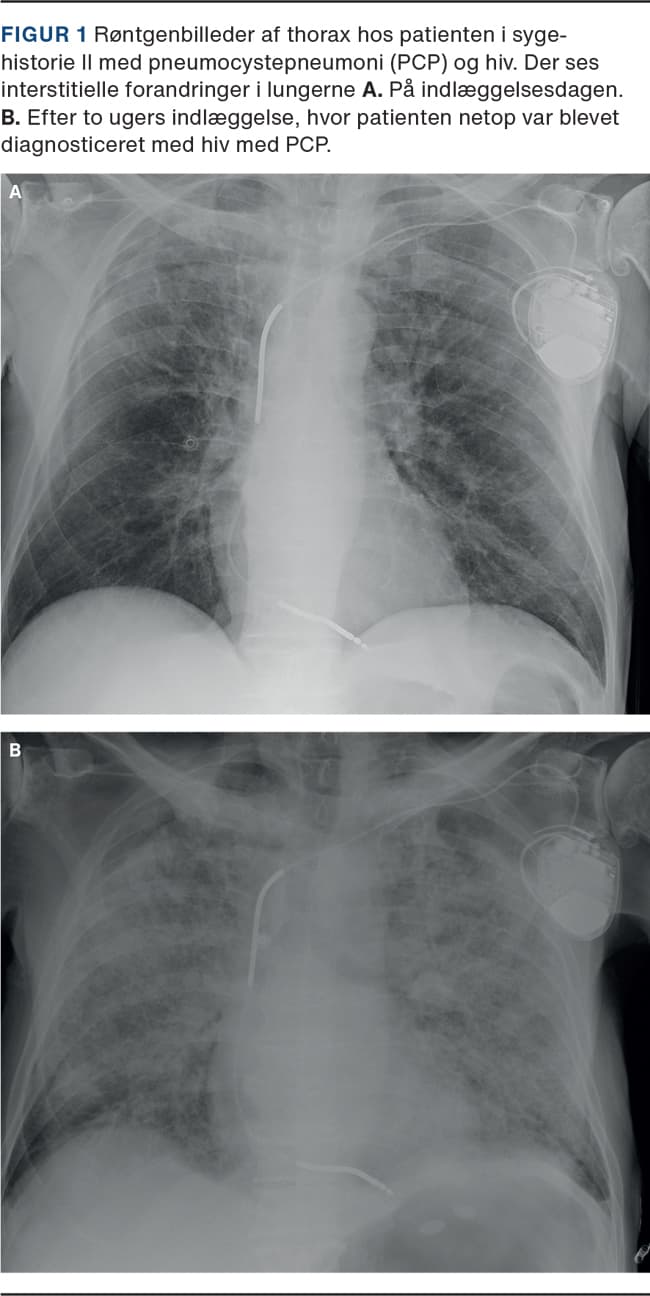

II. En 71-årig mand, som havde kronisk obstruktiv lungesygdom (KOL) og iskæmisk hjertesygdom, blev indlagt på en lungemedicinsk afdeling på mistanke om COVID-19. Han var igennem mange måneder blevet tiltagende træt, appetitløs og afkræftet og var nærmest bundet til sengen. Han havde hypoksi med en saturation på 92% og det parakliniske billede med lymfocytopeni, et CRP-niveau på 37 mg/l, anæmi, et LDH-niveau på 296 E/l og en røntgenundersøgelse af thorax (Figur 1), hvorpå der sås interstitielle forandringer, henledte mistanken på COVID-19. Trakealsekretet blev undersøgt, og han blev podet i alt fire gange for SARS-CoV-2. Alle test var negative. Hans tilstand forværredes under indlæggelsen, han blev delirøs og febril, hostede og fik progredierende behov for ilt. Han blev sat i bredspektret antibiotisk behandling uden effekt, udredt for KOL-eksacerbation og akut myokardieinfarkt uden ST-elevation, og der var mistanke om en underliggende malign tilstand. Efter to ugers indlæggelse blev PCP overvejet som differentialdiagnose, og polymerasekædereaktionstest for pneumocyster på trakealsekret var positiv. Efter konference med en infektionsmedicinsk afdeling blev udført hiv-kviktest, der udkom positiv. Patienten blev overflyttet til en infektionsmedicinsk afdeling, hvor der blev iværksat behandling for PCP og hiv. CD4-tallet var 14 celler/µl.

PCP ligner både klinisk og paraklinisk COVID-19 med hypoksi, interstielle forandringer på røntgenbilleder, forhøjet LDH-niveau og lymfocytopeni. Begge patienter havde dog symptomer, der ikke oplagt skyldtes COVID-19. De havde tegn til underliggende sygdom og var nærmest kakektiske ved indlæggelsen, og patienten i sygehistorie I havde oral candidiasis.